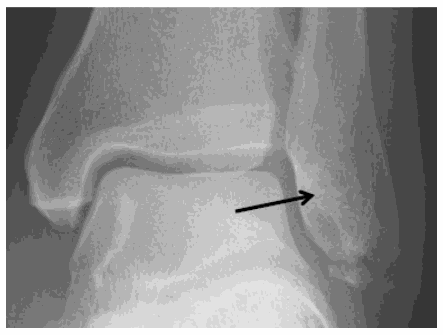

- You have had a simple soft tissue injury to your ankle. As part of this you may also have had a “chipped bone” / “avulsion fracture”.